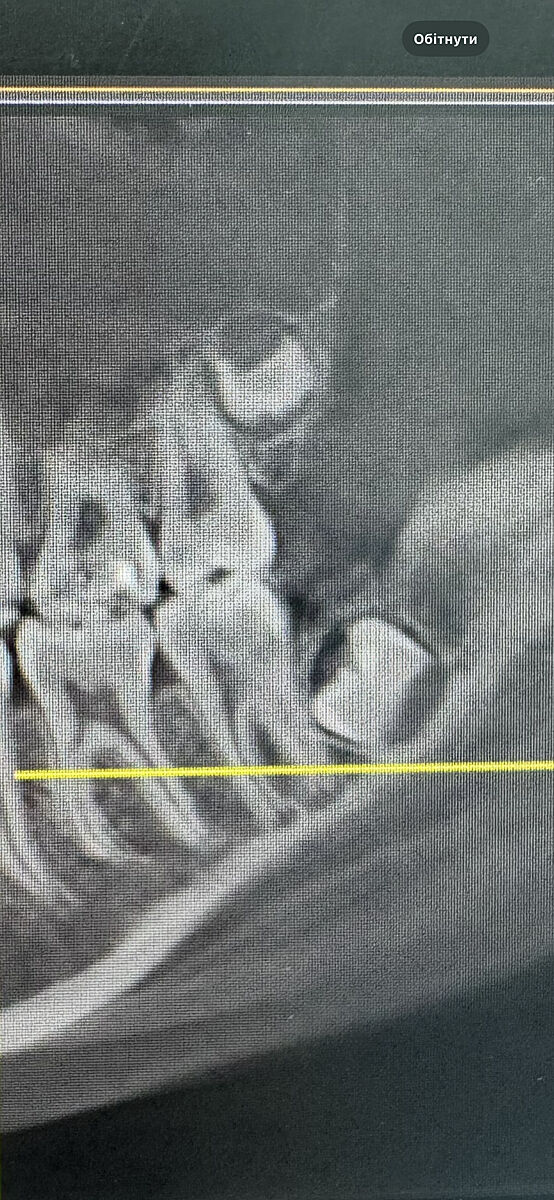

Ще таке фото

Хто знає - прокоментуйте будь ласка

Покажіть панораму доньки